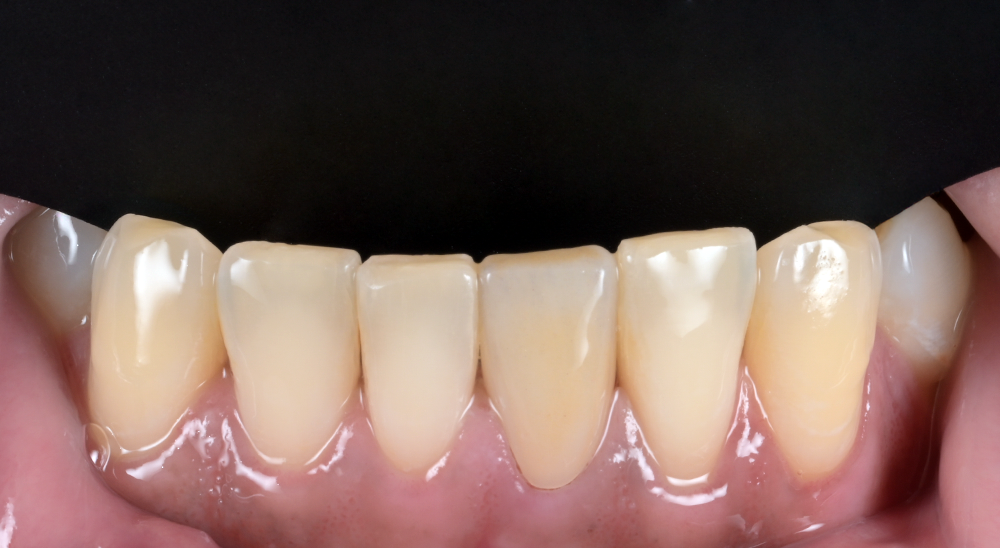

기능과 조화의 균형을 생각하며

심미 보철

앞니의 기능적, 심미적 개선을 돕는 모든 과정에서

보존의 원칙을 중요하게 생각합니다.